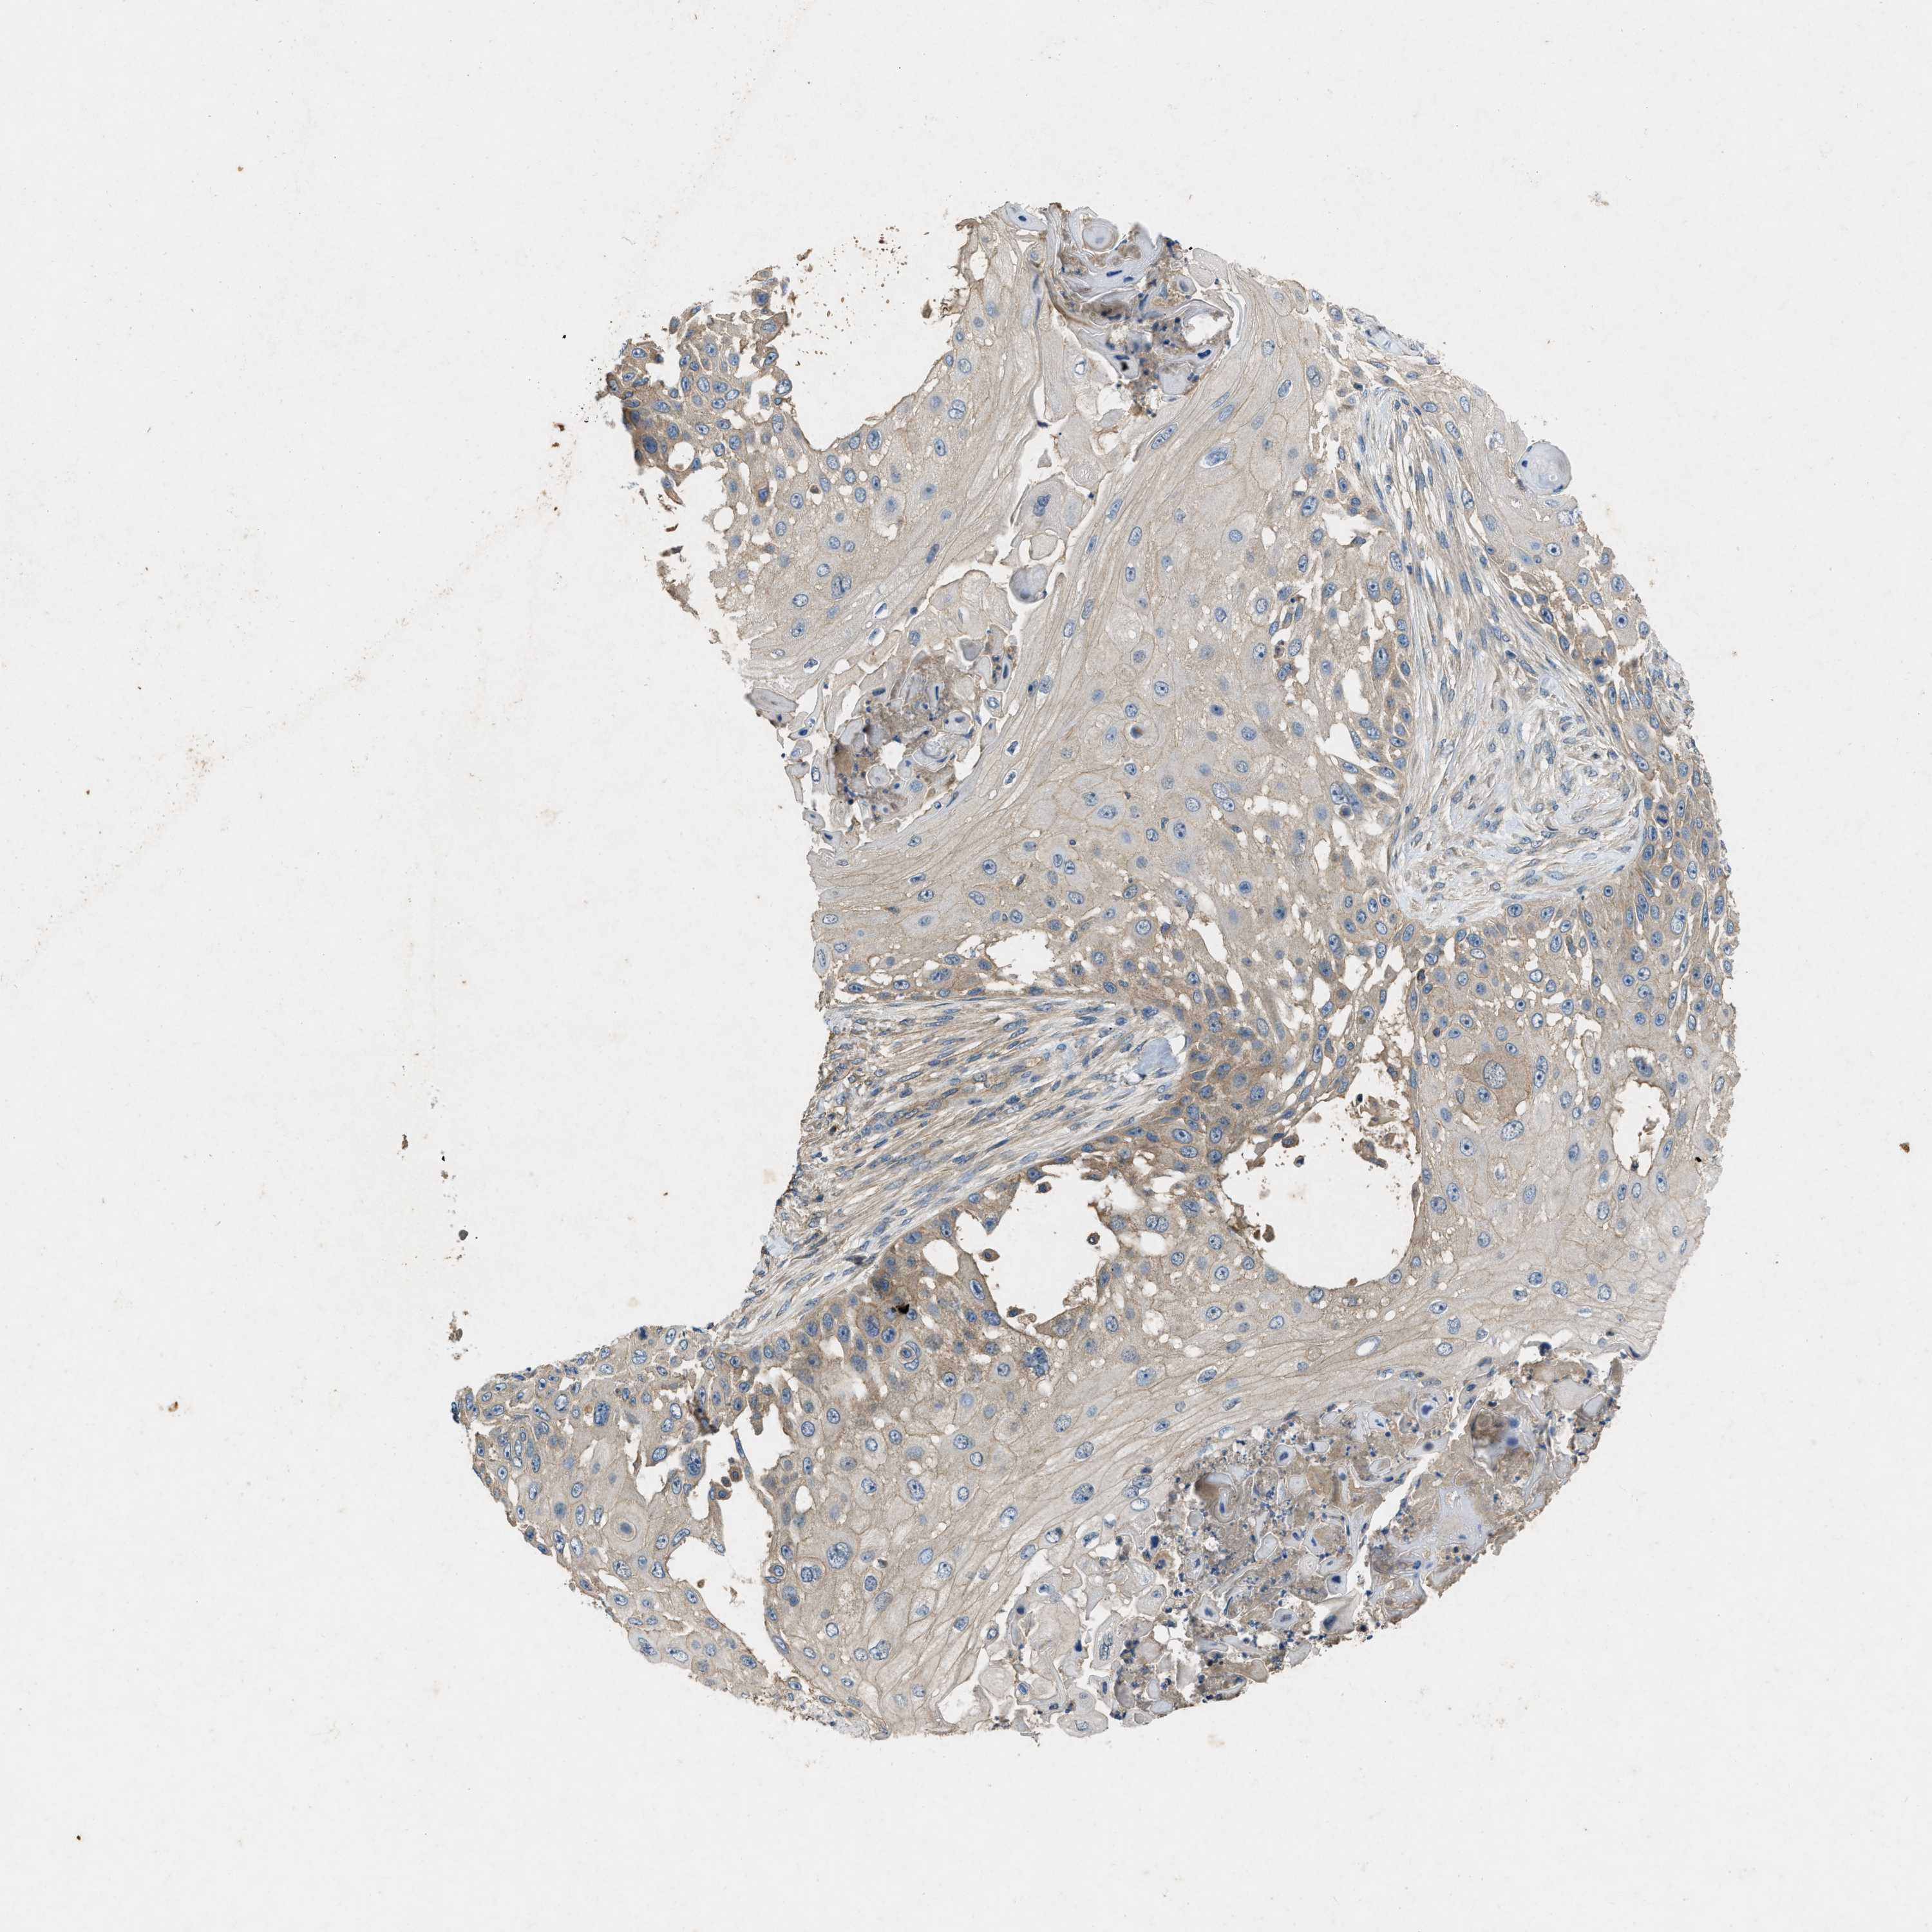

SKIN CANCER - Protein expressioni

A mouse-over function shows sample information and annotation data. Click on an image to view it in a full screen mode. Samples can be filtered based on level of antibody staining by selecting one or several of the following categories: high, medium, low and not detected. The assay and annotation is described here.

Each image is clickable and will lead to virtual microscopy that enables deeper exploration of all samples and also displays staining intensity scores, fraction scores and subcellular localization as well as patient and tissue information for each sample.

Antibody CAB018581

Squamous cell carcinoma, NOS